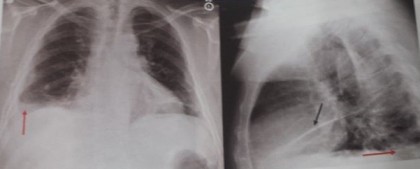

Imaginea radiologică patologică a cutiei toracice

Cutia toracică poate prezenta modificări de formă, de dimensiune sau modificări mixte de formă şi dimensiuni.

Modificările formei cutiei toracice ne pot da aspecte variate: torace cifotic, torace paralitic, emfizematos, astenic sau asimetric.

Modificările de dimensiuni pot fi simetrice şi asimetrice.